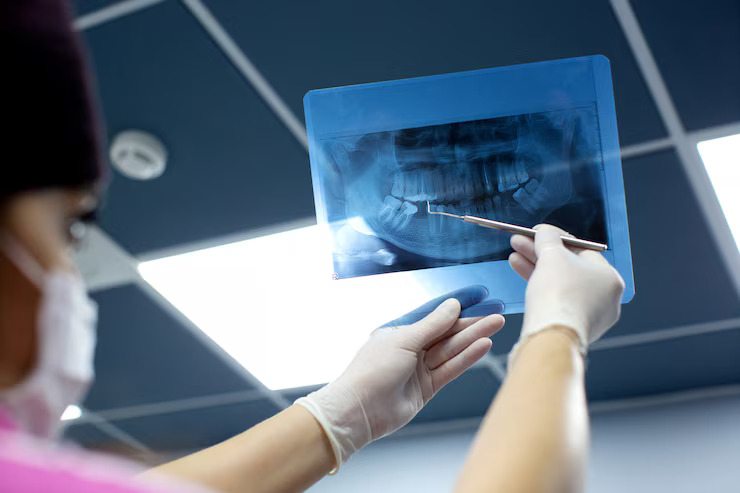

At Prime Gupta Dental Care Hospital, we use advanced digital X-ray technology to capture detailed images of your teeth and jaw. These X-rays help us diagnose hidden dental issues such as cavities, infections, bone loss, or impacted teeth that are not visible during a regular exam.

Digital X-rays are fast, safe, and involve minimal radiation. With instant results, we can plan your treatment more accurately and ensure early detection of potential problems for better oral health outcomes.